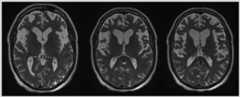

Case 5-2

A 69-year-old right-handed retired secretary was referred for a neurologic consultation for difficulties with “memory” and behavior. She had a long history of anxiety and depression that had been managed by medications until 2 years prior to presentation, when she was dismissed from her volunteer job for “lacking control.” Her family noted trouble with word comprehension, as the patient would ask, “What is a screwdriver?” and “What is a buffet?” Circumlocutions were noted in her descriptions, such as describing a pizza as a “round thing.” This was followed by lack of recognition of objects. For example, when her husband handed her an ice cream cone, she grabbed at the ice cream on top rather than from the cone. Recently, she had not recognized her niece and nephew or herself in photographs. The patient stopped initiating household chores, such as doing the dishes or laundry, and appeared confused when attempting such tasks. According to her husband, she was “always walking, pacing, or standing.” She became very self-centered and seemed to lack appreciation of others’ needs. She became fixated on daily routines even if inconvenient to others. Her personal hygiene declined. Family history was notable for multiple family members on her mother’s side with anxiety and depression. There was no known history of neurodegenerative dementia or amyotrophic lateral sclerosis in any family members.

On examination, while her speech rate was generally high, she used frequent fillers, such as “thing” or “da da da.” Her responses to direct questions were tangential. The remainder of her neurologic examination was normal, including the absence of frontal release signs. On further cognitive testing, she scored 8 out of 30 on the Mini-Mental State Examination (MMSE), typically not understanding the question being asked. Her clock drawing skills were reasonably preserved. Semantic fluency was severely impaired with only two animals named in 1 minute. In contrast, phonemic fluency was only mildly impaired with a total of 20 F-A-S Test words named over the 3 minutes (patient was given 1 minute to list words beginning with the letterF, followed by 1 minute to list words beginning withA, and then 1 minute to list words beginning with the letterS). Naming on the Western Aphasia Battery was impaired, with only 11 out of 20 items correct and some evidence of visual object agnosia, including nonrecognition of a pipe. Deficits in semantic association were also demonstrated on the Pyramid and Palm Trees Test. Trail Making B test was normal at the 50th percentile.

Review of a recently performed brain MRI demonstrated severe anterior left temporal lobe atrophy and moderate atrophy of the right temporal pole (Figure 5-3). A diagnosis of semantic variant primary progressive aphasia was made.

Figure 5-3.

Imaging of the patient inCase 5-2.A, Axial fluid-attenuated inversion recovery (FLAIR) MRI demonstrating left temporal pole atrophy suggestive of semantic variant primary progressive aphasia.B, With disease progression, severe atrophy is observed in the left temporal pole as well as significant atrophy in the right temporal pole on axial FLAIR MRI.

Comment. This patient demonstrates a classic presentation of semantic variant primary progressive aphasia. Often, the family members may identify the chief complaint as memory deficits, but with careful assessment, it is clear that loss of word meaning and comprehension deficits underlie the observed changes. Behavioral features are usually present early on and progress with increasing atrophy of the right temporal lobe.

Neuroimaging

Atrophy of the dominant anterior temporal pole is the hallmark finding in semantic variant PPA (Figure 5-3).24 While involvement is typically asymmetric at onset, over time the contralateral temporal lobe is also affected.